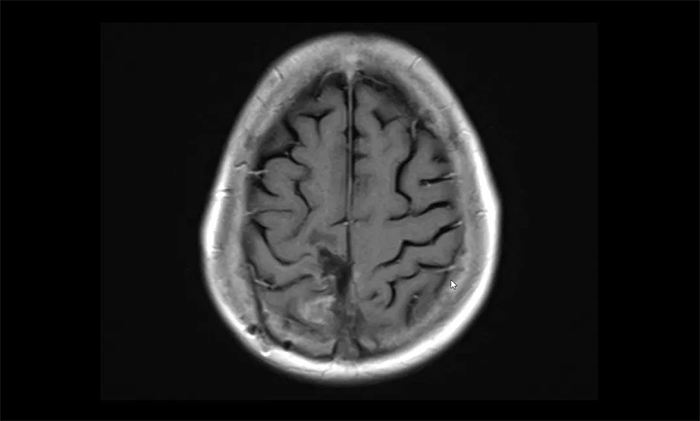

▲ 治療后檢查顯示,病灶明顯縮小

近期患者復(fù)查,腫瘤病灶較治療前明顯縮小,周圍水腫明顯減輕;颊咴酒c的左側(cè)肢體恢復(fù)了活動(dòng)能力,擺脫了輪椅,可自行走動(dòng),日常生活基本可自理。